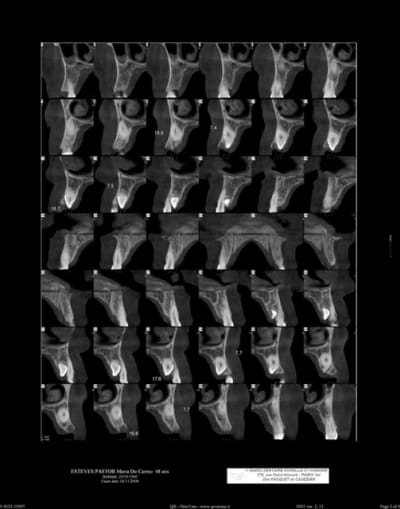

voir scan ci-joint

maintenant faut pas oulier que extraire les canines peut être extrêment délabrant et que poser des implants derrière c'est pas forcément une évidence. Pense aussi que les incisives sont en rapport étroites avec les canines et que tu peux les léser au passage.

Tu fais de la chir donc faire un lambeau palatin ne devrait pas poser de problème. SOit elles viennent toutes seules soit faut dégager autour pour libérer la ligne de plus grand contour sans toucher les racines adjacentes. Les extractions de ce genre pour moi y'a pas de technique miracle, c'est au cas par cas après avoir ouvert le lambeau.

Je ne les fragmenterais pas trop vite pour garder une prise auniveau coronaire.

Le problème c'est les extraire en conservant l'os autour mais vu les morceaux c'est pas gagner, en espérant qu'il n'y pas de plages d'ankylose.

je vais regarder tes scan plus précisement et si j'ai une idée ...